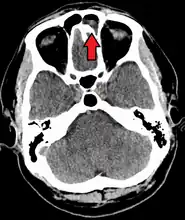

For sinusitis lasting more than 12 weeks, a CT scan is recommended.[47] On a CT scan, acute sinus secretions have a radiodensity of 10 to 25 Hounsfield units (HU), but in a more chronic state they become more viscous, with a radiodensity of 30 to 60 HU.[49]

MRI image showing sinusitis. Edema and mucosal thickening appears in both maxillary sinuses.